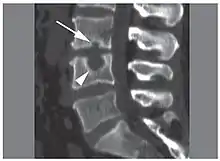

CT scan in the sagittal plane of two Schmorl's nodes. The small Schmorl's node at the inferior endplate of the L3 vertebral body (arrow) has typical features, being broad-based at the endplate, with well-defined contours and thin marginal sclerosis. A large and less typical Schmorl's node (arrowhead) is observed at the superior endplate of L4.[3]